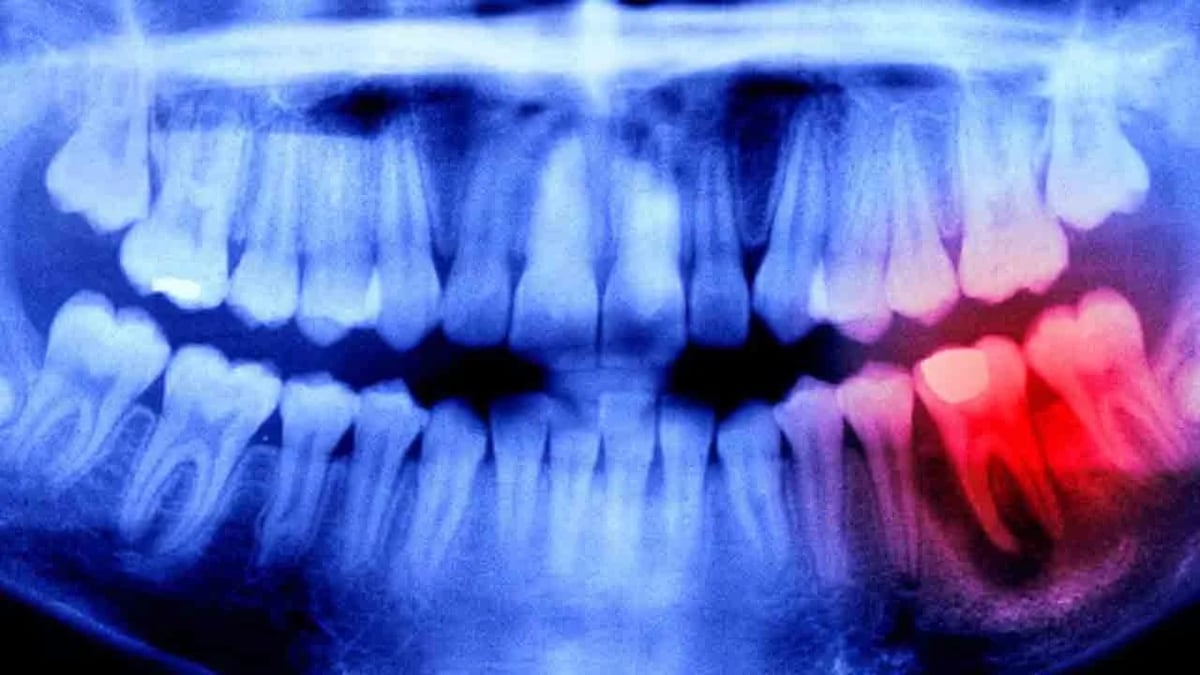

Araştırma ekibi, insan çenesinde bulunan ancak gelişimini tamamlamayan üçüncü set dişlerin büyümesini sınırlayan genetik engelleri saptadı. Geliştirilen bu özel antikor ilacı, diş oluşumunu durduran proteini etkisiz kılarak vücudun kendi onarım mekanizmasını başlattı.

Bu biyolojik müdahale sayesinde, yetişkin bireylerin çenesinde saklı kalan tomurcukların yeni dişler oluşturması için gerekli zemin hazırlandı. Bilim insanları, bu yöntemin implant ve protez gibi yapay çözümlere doğal bir alternatif sunduğunu belirtti.